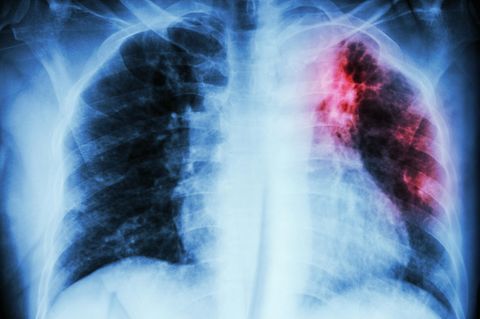

Ansteckende Infektionskrankheit Tuberkulose - 70 positive Tests in Dresden

Nach Angaben des Dresdner Gesundheitsamtes wurden 70 Personen positiv auf Tuberkulose getestet. Eine Person befindet sich zur weiteren Abklärung im Krankenhaus.

Als im vergangenen September ein Fall von Lungentuberkulose an einem Dresdner Gymnasium bekannt wurde, war die Aufregung groß: Diese Form von Tbc gilt als hochansteckend. Das Gesundheitsamt entschloss sich deshalb vorsorglich dazu, mehr als 1000 Schüler, Lehrer und Mitarbeiter auf eine mögliche Infektion zu untersuchen. Das Ergebnis der groß angelegten Untersuchung veröffentlichte das Gesundheitsamt nun auf seiner Homepage: Demnach konnte der Tuberkulose-Erreger bei 70 Menschen nachgewiesen werden. Ansteckend waren diese wohl aber nicht.

Die positiv getesteten Menschen waren nicht an Tuberkulose erkrankt, heißt es in der Mitteilung des Gesundheitsamtes. Das Testergebnis besagt demnach lediglich, dass sie Kontakt zu ansteckungsfähigen Personen hatten und der Erreger übertragen wurde. Den positiv getesteten Schülern, Lehrern und Mitarbeiter wurde eine präventive Behandlung mit Antibiotika empfohlen. "60 Personen von ihnen haben die Prävention inzwischen erfolgreich abgeschlossen", schreibt das Gesundheitsamt.

Tuberkulose-Verdacht - eine Person befindet sich im Krankenhaus

Über den Gesundheitszustand einer Person herrscht derzeit Unklarheit: Bei ihr habe es trotz Prävention einen "auffälligen Befund" gegeben. Sie sei im Krankenhaus. Ob die Person tatsächlich an Tuberkulose erkrankt ist und möglicherweise ansteckend ist, steht derzeit noch nicht fest. Erste Ergebnisse liegen demnach in sechs Wochen vor.

An der Lungenkrankheit Tuberkulose sind früher viele Menschen gestorben. Heute gilt Tbc aber als gut zu behandeln. Die Krankheit ist aber hochansteckend und muss deshalb beim Gesundheitsamt gemeldet werden. Tuberkulose wird durch Tuberkulosebakterien hervorgerufen. Eine Ansteckung erfolgt meist durch das Einatmen von infektiösen Tröpfchen.

Bricht die Infektionskrankheit aus, kann sich unter anderem durch Fieber, Husten, Nachtschweiß und Appetitlosigkeit bemerkbar machen. Sie kann aber auch symptomlos verlaufen. Eine Tuberkulose ist mit einer medikamentösen Therapie heilbar. Schwere Verläufe sind selten.